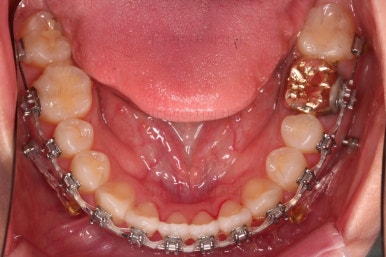

5. 치료의 종료

부산치아교정잘하는곳 키다리아저씨치과에서 치료를 종료했을 때의 사진입니다.

위아랫니가 가지런해졌고요.

다시 틀어지지 말라고 적절한 유지장치를 구성합니다.

보철 치아의 위치/크기로 인해 100% 중앙선은 맞기 힘드나 가장 잘 맞추어 놨고, 앞니의 각도도 매우 좋아졌습니다.

아래 앞니도 단순히 머리 부분만 뒤로 눕힌 것이 아니라 뿌리까지 뒤로 당겨왔고요.